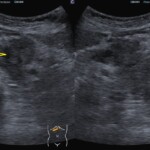

① 腹部エコーで膵臓がんが「直接」見える場合

腹部エコーでは、条件が整えば膵臓の腫瘍そのものを直接確認できることがあります。

特に、体格や腸管ガスの影響が少ない方では、膵臓の形や内部構造が比較的はっきりと描出されます。

膵臓がんは、周囲の正常な膵組織と比べて低エコー(黒っぽく)に見えることが多く、

腫瘤として認識される場合があります。

早期の段階でこのような所見を捉えられれば、次の精密検査へ速やかにつなげることができます。

@膵臓がん

ただし、膵臓は胃や腸の奥に位置する臓器であり、すべての患者さんで常に明瞭に見えるわけではありません。